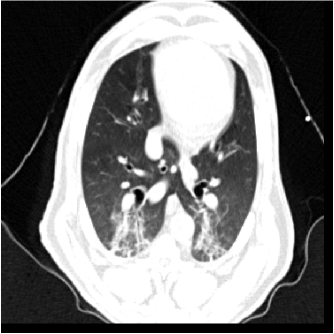

For each animal, approximately 200 automatically identified landmarks within the lungs are used to compute registration accuracy. The landmarks are widely distributed throughout the lung regions. Figure 5 shows an example of the distribution of the landmarks in animal D for both the and images. The coordinate of each landmark location is recorded for each image data set before and after registration for all four animals. Figure 6 shows the landmark distance before and after registration for four animals. The grey boxes show the magnitude of respiratory motion during the tidal breathing. For all four animals, before registration, the average landmark distance is 6.6 mm with a minimum distance of 1.0 mm, maximum distance of 14.6 mm, and standard deviation of 2.42 mm. After registration, the average landmark distance is 0.4 mm with a minimum distance of 0.1 mm, a maximum distance of 1.6 mm, and a standard deviation 0.29 mm. The trends for all animals are consistent and the results demonstrate that the registrations produced good anatomic correspondences. All registrations were examined and it was confirmed that all Jacobian values had positive values.

Figure 5(a) shows the location of the (Xe-CT) slab overlaid on the image. Figure 7 shows an example of the image registration result from the image to the image. The first row shows the misalignment between the images before image registration. Though the images were acquired without moving the animal between the scans, there is still non-rigid deformation between scans as shown in Fig 7(d), as the black and white regions represent the large intensity difference between Fig. 7(a) and (b). In addition, the slice thicknesses were quite different which causes partial volume artifacts. After image registration, the image is aligned to the image, and the resulting difference image (shown in Fig. 7(e)) is near zero. The transformation from the to the image allows us to map the Xe-CT sV into the coordinate system of image. Note that since the regions outside the lung are not included in the registration process, the mediastinum and other body tissues are not aligned. Also note that the dorsal region of the lung shows a intensity difference after registration. This is due mainly to the gradual progression of atelectasis and tissue edema during the course of the experiment.